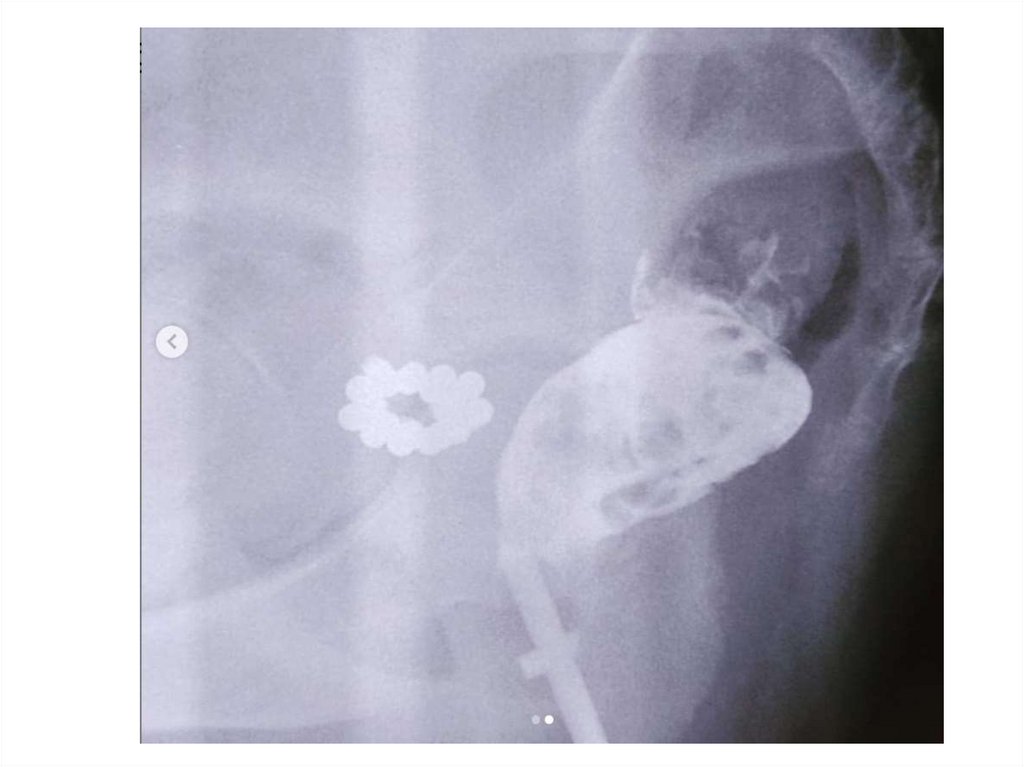

Цистография

Контрастное исследование

мочевого пузыря.

• Пузырно-мочеточниковый

рефлюкс?

• Форма

• Контуры

• Дефекты контрастирования

• Грыжа, дивертикул

Пузырно-мочеточниковый

рефлюкс (ПМР)